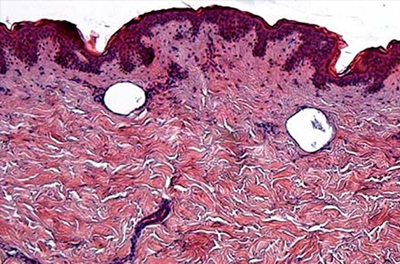

박피성 프락셀레이저는 강력한 레이저로 피부의 표피를 벗겨내고 그 자리에 재생 반응을 유도하여 손상 부위를 차오르게 만드는 방식입니다.

표피 손상이 있는 비박피성 프락셀은 표피에 심한 손상을 주지 않을 정도의 열에너지를 타겟 부위에 조사하여 손상된 피부 조직을 서서히 가열시켜 재생 반응을 유도하는 프락셀 방식입니다.

앞서 언급한 박피성 프락셀은 피부 조직 자체를 파괴해 재생 반응을 얻는 것과 달리 비박피성 프락셀은 조직 변성과 피부 재생 반응을 유도하여 흉터나 모공을 개선하는데요. 표피와 진피에 적당한 손상으로 효과를 얻는다는 차이가 있습니다.

앞서 언급한 비박피성 프락셀레이저는 표피, 진피에 적은 손상으로 효과를 얻는 방식이었다면, 표피 손상이 없는 비박피성 프락셀레이저 방식은 표피 자체에 전혀 영향을 주지 않고 타겟층인 진피에만 열에너지를 전달하는 방식입니다.